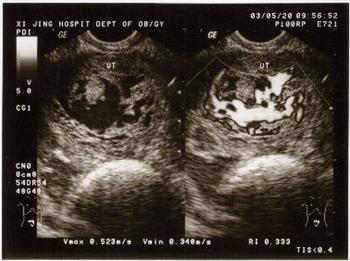

B超所示:全腹探及一巨大包块(上至剑突下3cm,下至盆腔,两侧至侧腹),边尚清,肿块的大部分呈细小的低回声及无回声区与光带相间的蜂窝状,肿块的左上部分及右下部分呈囊性多房样改变,子宫、附件显示不清。提示:腹盆腔肿块囊实混合性,其病理性质待查(卵巢肿瘤?)。

剖腹探查:妇科行剖腹探查术。术中所见:子宫增大如妊娠7个月大小,宫壁菲薄,宫腔内充满着细小的葡萄子样水泡。双侧卵巢增大,呈囊性多房样改变。

病理诊断:恶性葡萄胎,双侧卵巢浆液性囊腺瘤。

恶性葡萄胎为葡萄胎组织侵入子宫肌层,多数在葡萄胎清除术后6个月发生。测尿HCG阳性。其典型声像图表现为:子宫内或宫壁内呈蜂窝状或海绵状改变。本例恶性葡萄胎术前临床及外院、本院B超均误诊为卵巢肿瘤,分析原因有:

②声像图表现复杂。宫腔内虽有典型葡萄胎的蜂窝状改变,但因子宫巨大,宫壁菲薄而难以判断该病变来源于子宫;又因子宫巨大压迫卵巢,使子宫和卵巢紧贴在一起没有分界而将子宫内的蜂窝状回声与两侧卵巢的多囊性回声误认为是同一肿块内的不同回声,从而使声像图表现复杂化,造成诊断的困难。